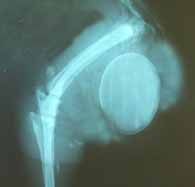

雄のアヒルでは、生殖器 (陰茎) を体内に戻すことができないため、陰茎が脱出することがあります。二次的な細菌汚染や不可逆的な損傷などの合併症を避けるために、注意が必要です。

陰茎が体外に出ると、進行期には腫大、腫脹、乾燥、潰瘍化、壊死に至るリスクがあります。